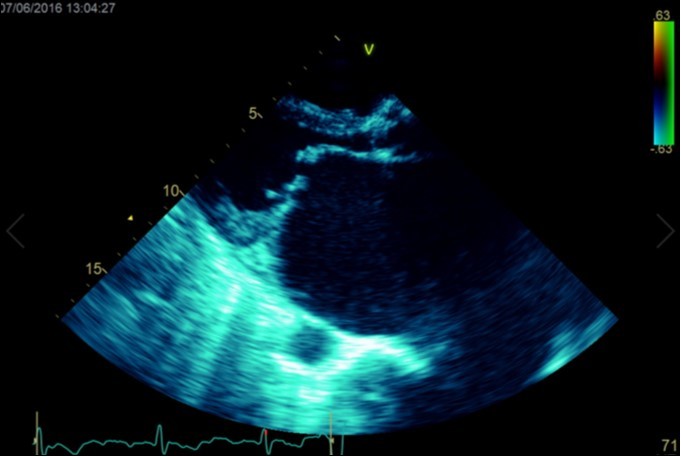

A dramatically dilated left atrium was seen on a TTE (see Figure 2a, Figure 2b, Figure 2c, and Figure 2d). Severe mitral stenosis with associated regurgitation was evident, with a mean gradient across the valve of 11mmHg and a hyperdynamic left ventricle. The left atrial volume measured by Simpson’s biplane method (see Figure 2c) was 2108mL, or 1548.5 ml/m2, based on height 1.55 metres and weight 44 Kg. Normal left atrial volume in a woman is 16 - 34 ml/m21. The computed tomography scan (CT) chest AP view (see Figure 3) is also shown.

Figure 2b.Transthoracic echocardiogram Parasternal long axis view. Findings include severe mitral stenosis (‘hockey-stick’ appearance to mitral valves), raised left atrial pressure (interatrial septum fixed and bowed to right)